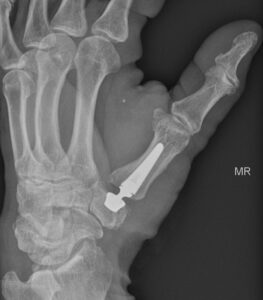

Postoperativ nach Einlage einer Touch-Prothese als Gelenkersatz. Das künstliche Gelenk ermöglicht nun die schmerzfreie Bewegung des Daumens in allen Achsen.